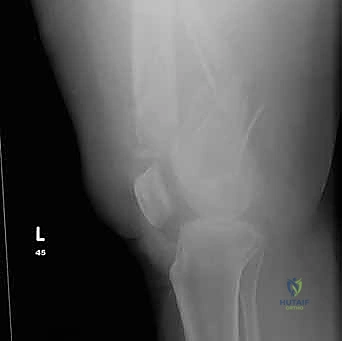

التشخيص الدقيق: حجر الأساس للعلاج الناجح

في عيادة الأستاذ الدكتور محمد هطيف في صنعاء، لا يتم ترك أي مجال للصدفة. يتم إجراء تقييم شامل يبدأ بـ:

- التقييم السريري المبدئي: فحص النبض والأعصاب للتأكد من عدم وجود إصابات وعائية أو عصبية مصاحبة.

- الأشعة السينية (X-Rays): أخذ صور من زوايا متعددة (أمامي خلفي، وجانبي) لتحديد موقع الكسر ونوعه.

- الأشعة المقطعية (CT Scan): وهي ضرورية جداً في كسور عظم الفخذ البعيدة، خاصة إذا كان الكسر يمتد إلى داخل مفصل الركبة (Intra-articular fractures). تساعد الأشعة المقطعية الدكتور هطيف على بناء نموذج ثلاثي الأبعاد للكسر، مما يسهل التخطيط الجراحي وتحديد أماكن وضع المسامير بدقة.